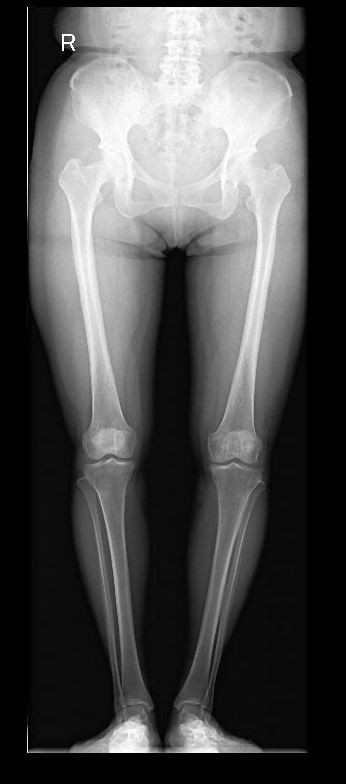

图7 膝骨关节炎全膝关节表面置换术a术前

图7 膝骨关节炎全膝关节表面置换术b术后

图7 :a图示双膝骨关节炎严重、外翻畸形。b图示右侧全膝关节表面置换术后